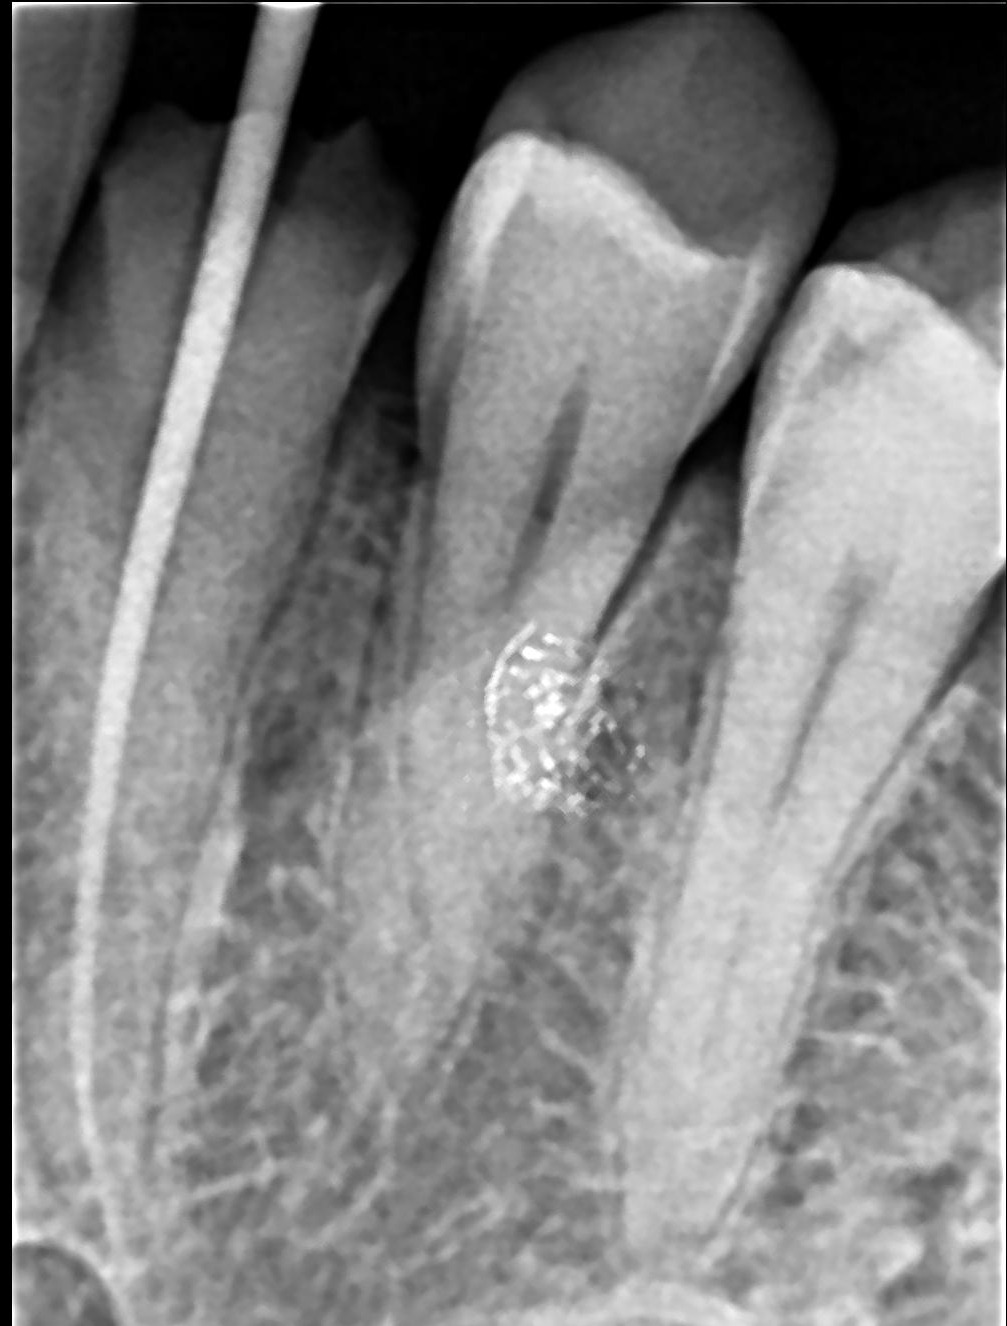

• Take digital X-rays

Step 3: Cleaning & Shaping

• Infected pulp is removed

• Canals cleaned using rotary instruments

Step 5: Filling the Canals

• Canals are sealed with biocompatible material

• Prevents reinfection